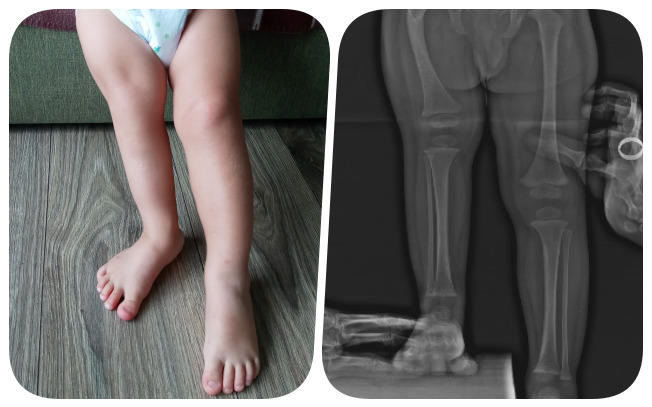

Nie wiedzieliśmy, że informacja, która całkowicie wywróciła nasz świat, dopiero nadejdzie. Kubuś urodził się z niedorozwojem kości udowej. Choroba pociąga za sobą szereg innych nieprawidłowości w budowie stawu biodrowego, a także znaczną różnicę w długości nóżek. Obecnie wynosi ona 8 centymetrów. Co gorsza, ostateczna różnica ma wynieść aż 21 centymetrów! Ratunkiem dla Kubusia są operacje, które mogą sprawić, że będzie sprawnym chłopcem! Doktor Paley daje nam 99% szans na całkowitą sprawnośc - tej szansy nie możemy zmarnować!

Prawdopodobnie nikt na świecie nie ma takiego doświadczenia w operowaniu ekstremalnie trudnych przypadków, jak dr Paley. Naszego syna czekają min. 4 operacje w ciągu najbliższego roku: 3 zabiegi biodra, jedna operacja kostki i prawdopodobnie stawu kolanowego. Nie zapominajmy o minimum 4 operacjach wydłużania kości udowej. Dr Paley zrobi pierwsze 4 zabiegi podczas jednej operacji. Ten wybitny amerykański specjalista przeprowadził już 1500 takich zabiegów, podczas gdy polscy lekarze czasem nigdy nie spotkają się z taką wadą…